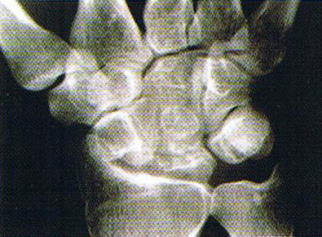

レントゲン写真

症状とレントゲン検査で月状骨の変形があれば、診断がつきます。MRI検査は早期診断に有用です。